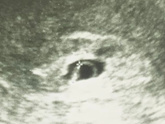

Вот он при хгч 2121

Потому что на 16дпп хгч был 455, на 20дпп у меня хгч был 1404 и это был очень маленький прирост, я пошла в слезах на узи, мне сказали все норм, виден ктр 0,7мм, я сдала хгч через 5 дней и он был 2121, я в панике, что прирост очень слабый пошла опять на узи сразу же, там ктр 4,4мм и есть сердцебиение! Это со мной что то не так? Сегодня сдала хгч 3608! Что со мной не так? Почему все не как у людей? Видимо я чудо женщина или просто не такая ?